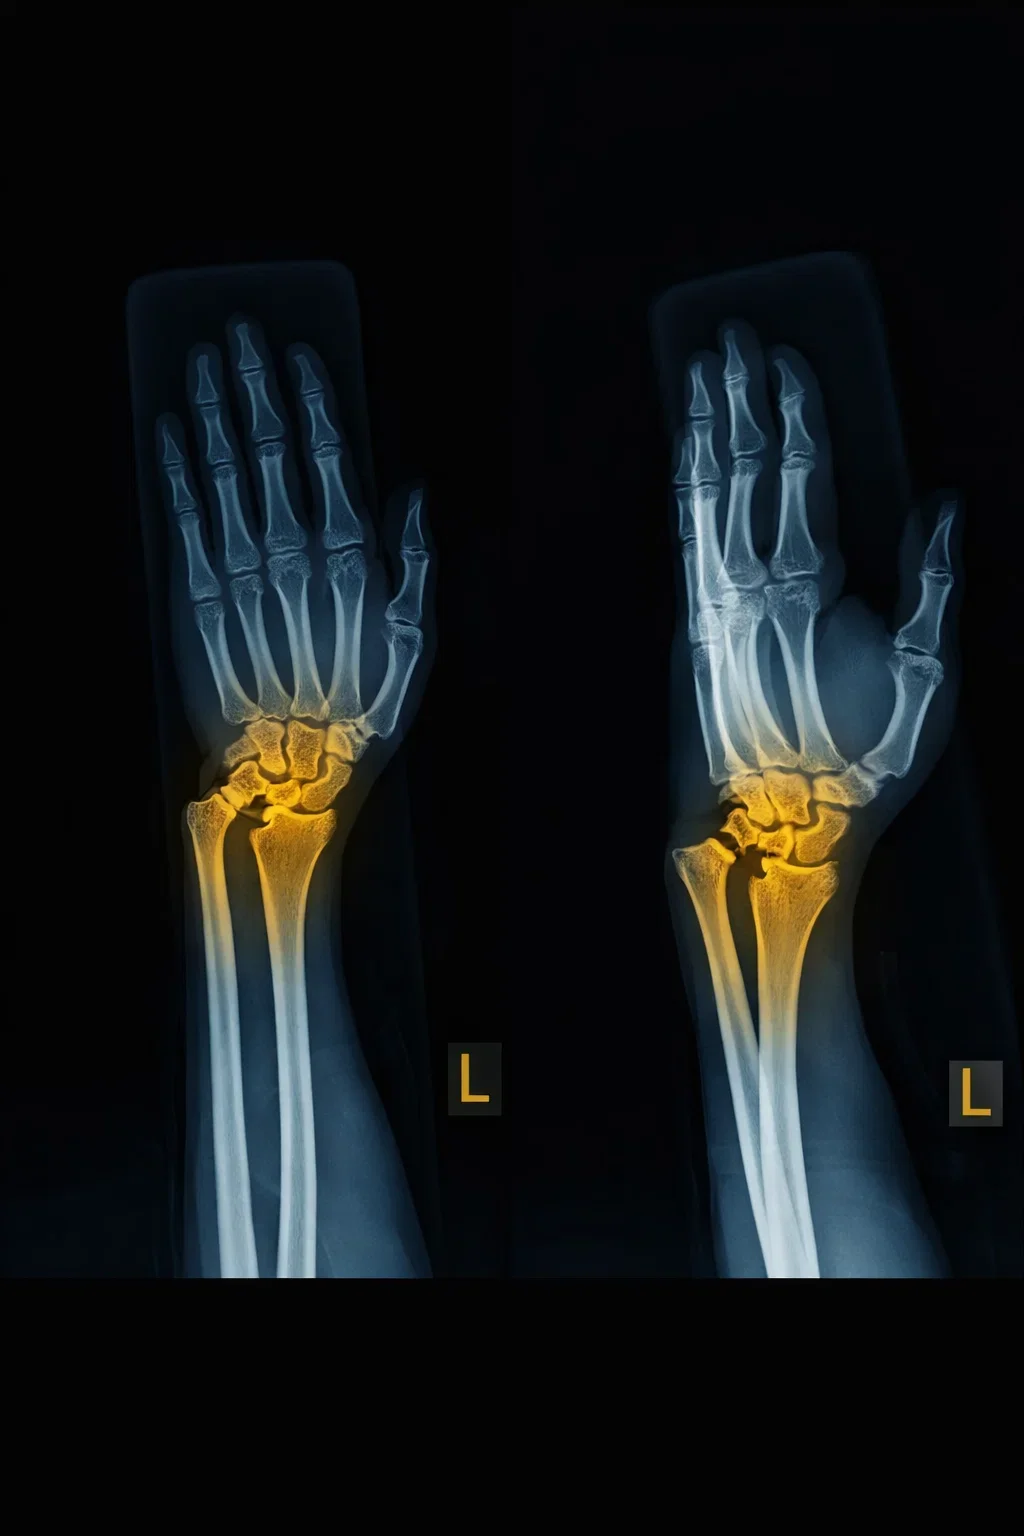

The wrist is comprised of two bones in the forearm, the radius and ulna, and eight tiny carpal bones in the palm. The bones meet to form multiple large and small joints. A wrist fracture refers to a break in one or more of these bones.

Your doctor performs a preliminary physical examination followed by imaging tests such as an X-ray of the wrist to diagnose a fracture and check alignment of the bones. Sometimes a CT scan may be ordered to gather more detail of the fracture, such as soft tissue, nerves or blood vessel injury. MRI may be performed to identify tiny fractures and ligament injuries.